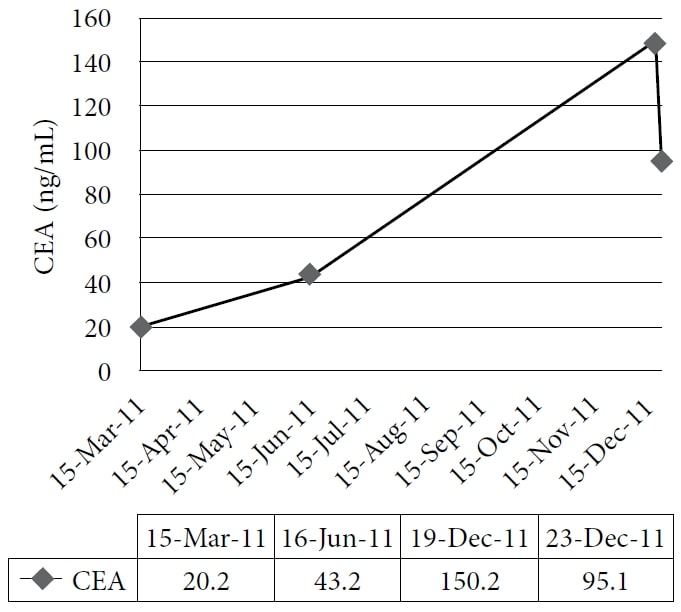

La paziente ha scelto di intraprendere un trattamento naturopatico presso la clinica di un autore, a partire da dicembre 2010. La terapia comprendeva rimedi omeopatici e IVC alla dose di 75 g due volte alla settimana, con un conseguente aumento del livello di energia e del peso. I farmaci e gli integratori in quel momento erano pantoprazolo, alfuzosina, metoprololo, ramipril, simvastatina, amlodipina, clopidogrel, vitamina D, complesso vitaminico B, acidophilus e acido α-lipoico. Il paziente ha continuato il trattamento fino al 2011 con un buon controllo dei sintomi; tuttavia, il suo CEA ha continuato ad aumentare. Una TAC effettuata nel novembre 2011 ha dimostrato una malattia epatica metastatica estesa e diffusa e numerosi noduli polmonari in espansione, coerenti con una progressione della malattia a intervalli. Il paziente ha quindi scelto di intraprendere un ciclo di prova di DCA per via endovenosa. Il 19 dicembre 2011 sono stati eseguiti gli esami del sangue di base, tra cui il CEA e gli enzimi epatici. La prima dose di 3000 mg (41 mg/kg) di DCA per via endovenosa è stata somministrata il 22 dicembre 2011, insieme a 50 g di IVC. Un test CEA era stato programmato per essere eseguito 4 settimane dopo, ma è stato erroneamente ripetuto 1 giorno dopo l’infusione, insieme alla misurazione degli enzimi epatici. È stata notata una rapida riduzione degli enzimi epatici e del CEA. (Vedi Figura 1 e Figura 2)

La figura mostra il graduale aumento dell’antigene carcinoembrionale (CEA) durante il trattamento naturopatico e la sua netta diminuzione dopo la somministrazione di dicloroacetato di sodio (DCA) per via endovenosa.

Il caso 1 illustra la risposta biochimica di un carcinoma metastatico del colon alla terapia DCA per via endovenosa, combinata con IVC ad alte dosi. In precedenza, il CEA del paziente era aumentato costantemente mentre utilizzava solo l’IVC per 10 mesi. Pertanto, la diminuzione del CEA può essere attribuita alla terapia con DCA. Poiché la letteratura riporta una potenziale riduzione del CEA di oltre il 50% entro 10 ore dalla metastatectomia epatica,40 un’ampia diminuzione del CEA a 1 giorno da qualsiasi altra terapia è plausibile se il tumore ha risposto rapidamente e non deve essere considerato un risultato errato. Inoltre, il rapido calo degli enzimi epatici è coerente con una riduzione del danno epatico derivante dalla morte delle cellule tumorali o dall’inibizione della crescita.